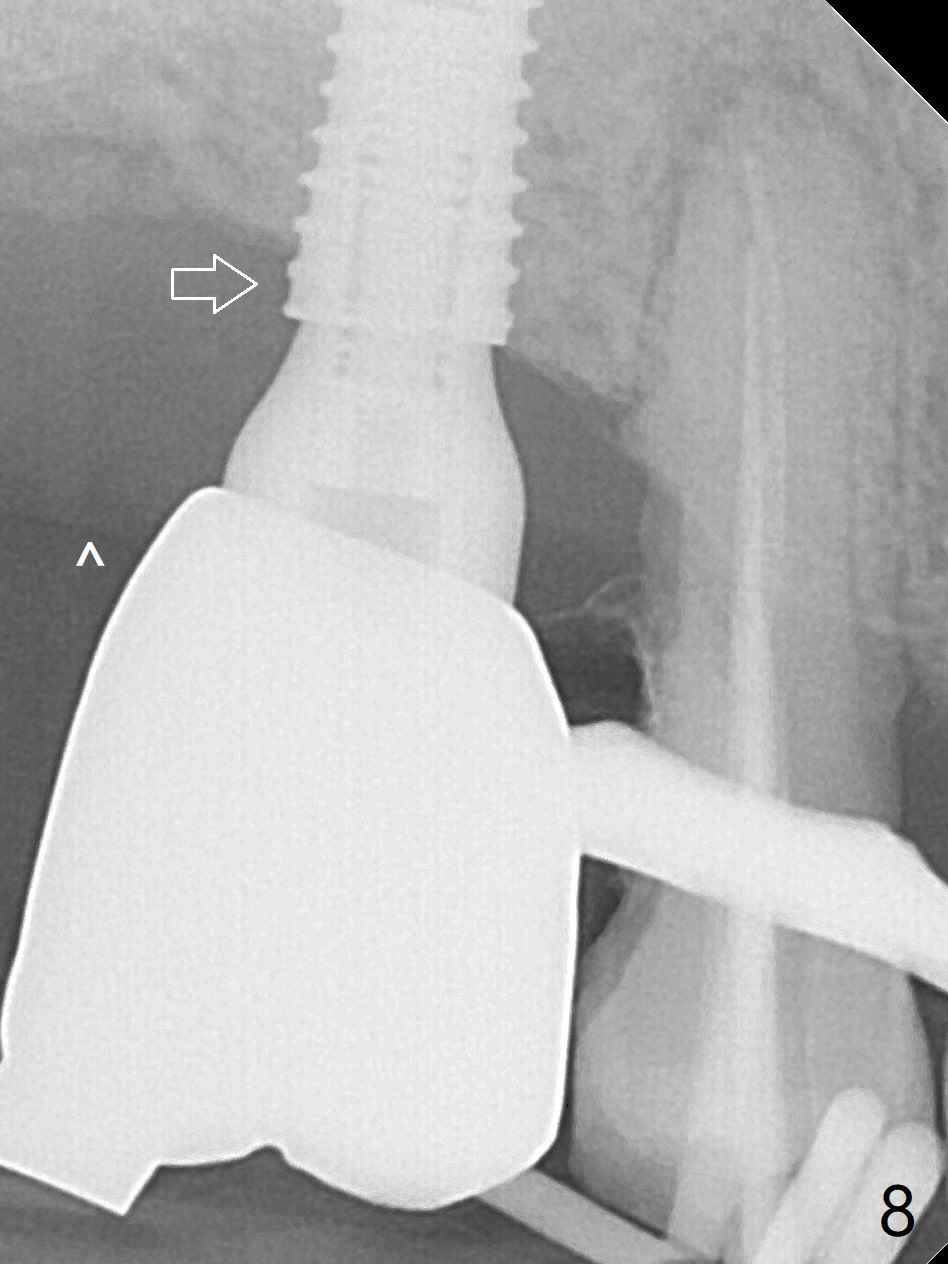

Bone Expansion Alternates with Drill

Since the ridge crest at #3 is narrow, Tatum bone scalpels are used to get access and initiate bone expansion, followed by bone blades and RT 2.  It seems that the osteotomy starts mesially; bone height being increased (Fig.1).  When the apical end of the osteotomy tilts mesially, more bone height is obtained.  Drills are alternatively applied because of the hard bone (Fig.2).  A 4x13 mm UF implant is placed initially with the distal threads unburied (Fig.3, >50 Ncm).  With further seating of the implant, a 5.5x5(4) mm abutment is used (Fig.4), which closes the access.  No suture is warranted.  An immediate provisional is fabricated for the patient's comfort and psychological effect.  In fact, the abutment cuff changes to 5 mm prior to temporarization.  There appears no bone loss <4 months postop (Fig.5).  Pulpitis develops at #4 due to DO caries 1 year 5 months post cementation (Fig.6 *).  The crown at #3 is removed for easy and conservative distal carious removal and Cavit temporary restoration to prevent sodium hypochlorite leakage.  Then occlusal access is made for pulpotomy.  When RCT finishes, no crown will be made, but occlusal reduction is required.    The patient returns for RCT 1 month later (Fig.7,8). Cavit remains in place (Fig.7 C).  Although 2 threads are exposed distal (Fig.8 arrow), there is no sign or symptom of periimplantitis, which may be related to the thick gingiva (arrowhead).  Return to Upper Molar Immediate Implant, IBS, #14 (Tissue Punch) Xin Wei, DDS, PhD, MS 1st edition 08/25/2017, last revision 09/08/2019